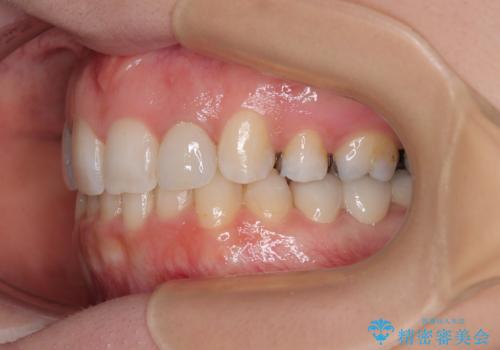

- 上顎前歯が叢生により前方に出ている状態や、全体的なむし歯を気にして来院された患者様です。

全体的にむし歯や欠損が多く、矯正治療とは別に処置が多く必要な口腔内でした。

抜歯したスペースがなかなか閉じず、治療に時間はかかりましたが、術前術後のむし歯治療と合わせて3年10ヶ月で治療を終えることができました。

途中結婚により遠方に引っ越しをされたため、むし歯治療は取り急ぎ目立つところをセラミッククラウンとしましたが、今後落ち着いてきたら他の部分も行っていく予定です。